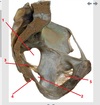

1

greater sciatic foramen

46

2

lesser sciatic foramen

47

3

sacrospinous ligament

48

4

sacrotuberous ligament

49

5

obturator foramen

50

51

52

53

54

55

lessor sciatic foramen